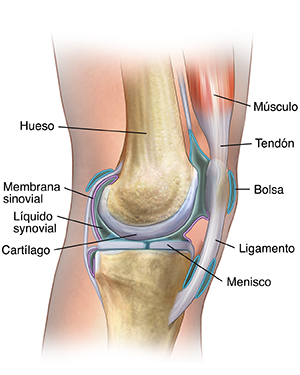

Anatomía de una articulación

Las articulaciones son las áreas donde se encuentran dos o más huesos. La mayoría de las articulaciones son móviles y permiten que los huesos se muevan. Las articulaciones constan de lo siguiente:

Cartílago. Un tipo de tejido que cubre la superficie de un hueso en la articulación. Los cartílagos ayudan a reducir la fricción del movimiento dentro de una articulación.

Membrana sinovial. Un tejido denominado membrana sinovial reviste la articulación y la sella en una cápsula articular. La membrana sinovial secreta el líquido sinovial (un fluido transparente y pegajoso) alrededor de la articulación para lubricarla.

Ligamentos. Existen ligamentos resistentes (bandas elásticas gruesas de tejido conectivo) que rodean la articulación para brindarle sostén y limitar su movimiento.

Tendones. Los tendones (otro tipo de tejido conectivo grueso) a cada lado de la articulación se unen a los músculos que controlan el movimiento de esa articulación.

Bursas. Las cavidades llenas de fluidos, denominadas bursas, entre los huesos, ligamentos y otras estructuras adyacentes, ayudan a amortiguar la fricción de la articulación.

Líquido sinovial. Líquido transparente y pegajoso secretado por la membrana sinovial.

Meniscos. Es una parte curva del cartílago de las rodillas y otras articulaciones.